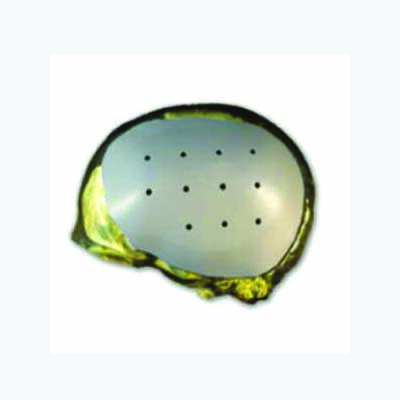

Medicad Implants is a state of the art technology firm specialized in providing customized solutions for hard tissue replacement and cranial implant in India. We are a synergy of motivated and experienced Engineers, Medical Practitioners and Designers striving to help surgeons for cranial implant india for their patients.

Skull injury as a result of tumor, decompressive trauma, infections or fractures from road accidents can be a life altering event. In addition to the physical changes that such an injury may bring, it could also lead to Psychological stress affecting the persons day to day activities.

Patient specific” Technology is one of the latest development in the medical field aimed at providing more accurate and lasting healthcare to patients. It synergically ties the medical imaging techniques with reverse engineering and rapid manufacturing concepts long being used in Aerospace and automobile fields to provide a unique solution on a case by case basis.